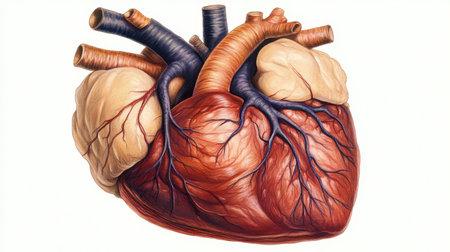

Рис. 2. Внутренняя структура сердца.

Сердце состоит из двух предсердий (правого и левого) и двух желудочков (также правого и левого) (рис. 2). Правая и левая половины сердца изолированы друг от друга и содержат различные виды крови: в правой стороне – венозную (бедную кислородом), в левой – артериальную (богатую кислородом). Кровь поступает в предсердия по венам, затем переходит в желудочки и далее в артерии.

Предотвращение обратного тока крови осуществляется клапанами сердца. Створчатые клапаны находятся между предсердиями и желудочками: трёхстворчатый клапан располагается справа, а двустворчатый – слева. Полулунные клапаны, закрывающие выход из желудочков, расположены между желудочками и артериями: легочный клапан справа и аортальный клапан слева (рис. 2, 3).

Сердце можно условно поделить на два этажа: верхний, где располагаются предсердия и крупные сосуды, и нижний, где находятся желудочки и также крупные сосуды. Между ними размещены клапаны, которые пропускают кровь только в одном направлении и закрываются плотно. Между правыми и левыми камерами сердца находятся перегородки, которые обычно не имеют отверстий, чтобы кровь не смешивалась. В правой части происходит циркуляция венозной крови, а в левой — артериальной.

Сердце человека (как и других млекопитающих) состоит из четырех камер, которые разделены сплошной перегородкой. Правая часть сердца содержит венозную кровь, тогда как левая — артериальную.

Правая и левая половины сердца разделены на предсердия и желудочки. Предсердия находятся в верхней части, а желудочки — в нижней.

Предсердия и желудочки отделены друг от друга створчатыми клапанами. В левой половине сердца располагается двустворчатый (митральный) клапан, а в правой — трехстворчатый.

Из левого желудочка выходит аорта — самая крупная артерия, а из правого желудочка — легочная артерия. На выходе из желудочков в этих крупных сосудах находятся полулунные клапаны.

Кровь выталкивается из сердца через полулунные клапаны: из левого желудочка (по аорте) — в большой круг кровообращения, из правого (по легочной артерии) — в малый круг. Полулунные клапаны пропускают кровь только в одном направлении (из сердца).